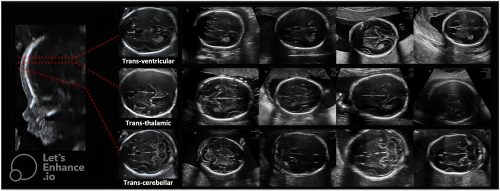

Hình 3. Siêu âm chi tiết não thai nhi